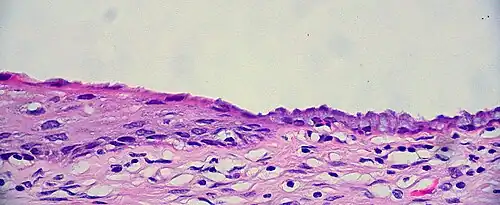

The squamocolumnar junction of the cervix: The ectocervix, with its stratified squamous epithelium, is visible on the left. Simple mucinous columnar epithelium, typical of the endocervix, is visible on the right. A layer of connective tissue is visible under both types of epithelium.

The cervical canal is generally lined by "endocervical mucosa" which consists of a single layer of mucinous columnar epithelium. However, after menopause, the functional squamocolumnar junction moves into the cervical canal, and hence the distal part of the cervical canal may be lined by stratified squamous epithelium (conforming to a "type 3 transformation zone").[2]